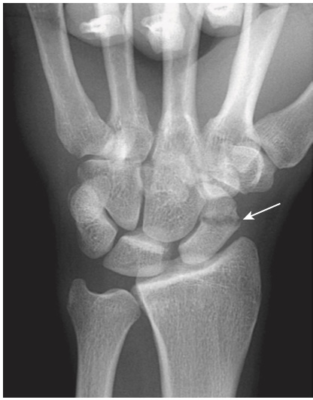

- Nghi ngờ gãy xương thuyền trên lâm sàng nếu đau ở hõm lào giải phẫu (anatomic snuff box) sau khi ngã chống tay.

- Tìm đường thấu quang mỏng trên phim (Tư thế xương thuyền: cổ tay duỗi 30⁰, nghiêng trụ 20⁰) (Hình 14).

- Gãy ngang eo xương thuyền có thể dẫn đến hoại tử vô mạch cực trên xương thuyền.

- Do đặc trưng phân bố mạch máu, gãy ngang eo xương thuyền ở cổ tay làm gián đoạn nguồn cung cấp máu đến cực trên, trong khi phần còn lại của xương cổ tay tiếp tục trải qua quá trình luân chuyển xương, mất khoáng. Kết quả là sự gia tăng tương đối rõ ràng về đậm độ xương của phần trên không được phân nuôi dưỡng so với phần còn lại của xương (Hình 15).